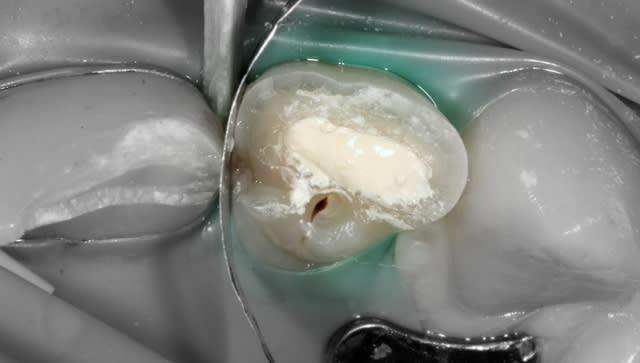

Enfant de 12 ans adressé par son dentiste le lendemain d'un trauma avec fracture de 21 et 22.

- 21 est une incisive mature mais jeune. Les cornes pulpaires sont très proéminentes et une fracture même d'apparence minime a donc une implication pulpaire directe. Il faut recouvrir en urgence le trait de fracture : ici par un CVIMAR (Fuji II LC). Une restauration par résine composite sera réalisée.

- 22 présente une exposition pulpaire ancienne de 20 heures. 20 heures donc que les germes buccaux contaminent directement la pulpe, heureusement jeune et donc avec un fort potentiel de défense.

Une pulpotomie partielle est réalisée afin d'éliminer le tissu le plus contaminé. De la Biodentine est utilisée ; son avantage par rapport au MTA est de ne pas noircir. Du CaOH aurait un taux de succès moindre.